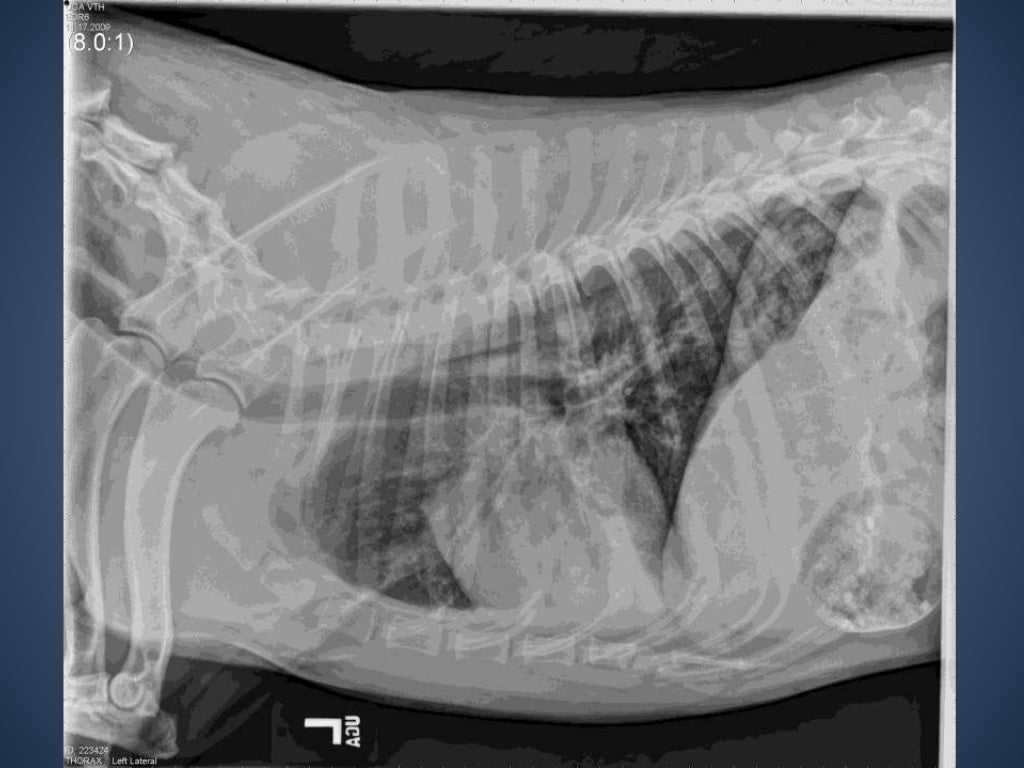

The Radiographic Approach to the Coughing Dog Does Kennel Cough Show Up On Xray Laboratory tests are usually normal. Tracheobronchitis is usually suspected whenever a dog demonstrates the distinctive harsh cough and has a history of exposure to other susceptible or affected dogs. Strong cough, often with a “honking” sound (the. Kennel cough results from an inflammation of the upper airways. If your dog has kennel cough, you may notice one or more of. Does Kennel Cough Show Up On Xray.